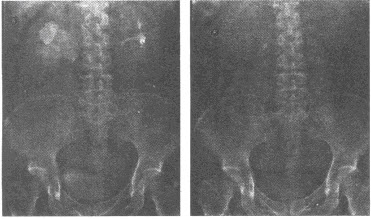

中年男性,腰部不适,伴有阵发性腹痛,行KUB和IVP检查,见下图,你考虑哪种疾病()

A:肾积水

B:肾肿瘤

C:输尿管积水

D:输尿管结石

E:肾囊肿